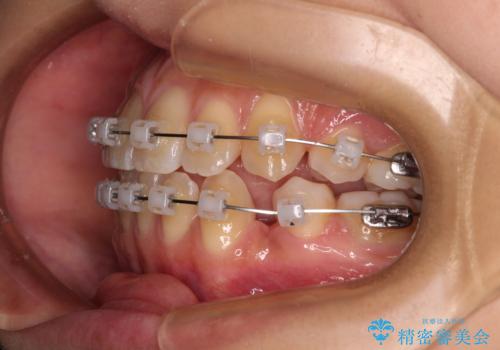

- クリアブラケット

- 上下顎前歯部の非接触(開咬)と下顎のデコボコを主訴に来院された患者様です。

下顎のデコボコの解消と、真ん中の位置を改善するために左下の小臼歯を抜歯することとしました。

また、開咬を改善するため臼歯部にアンカースクリューを用いて圧下する力をかけていきました。

舌のトレーニングは継続して行ってもらっているため、開咬や抜歯したスペースの後戻りはなく、経過は良好です。